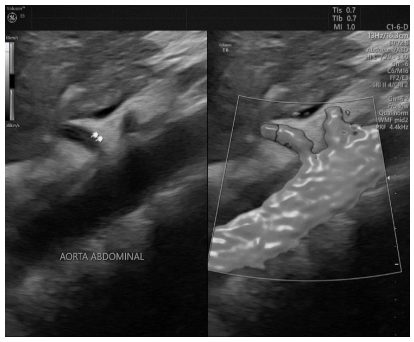

Qual estrutura está apontada na imagem a seguir e quais vasos se ramificam diretamente dela em condições habituais?